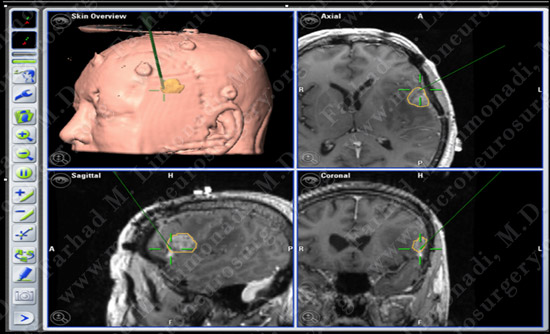

Computer Navigation

He underwent surgical resection of this tumor utilizing brain mapping, stereotactic and computer navigation, and intraoperative neurophysiological monitoring.